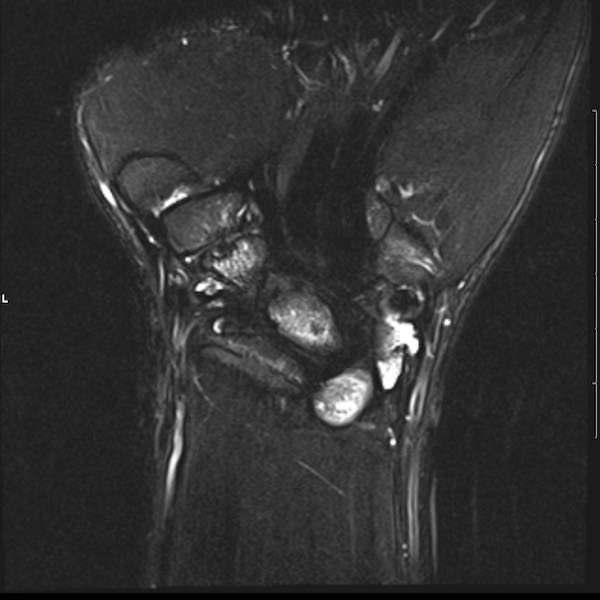

Tiếp tục xem hình ảnh MRI của bệnh nhân này.

Hình ảnh MRI:

Tràn dịch lan tỏa tất cả các khớp cổ tay.

Phù tủy xương lan tỏa tất cả các xương cổ tay.

Bào mòn xương, ví dụ tại xương thuyền, xương đầu và xương móc.

Phá hủy khe khớp và sụn khớp, rõ nhất tại khớp STT và CMC4/5.